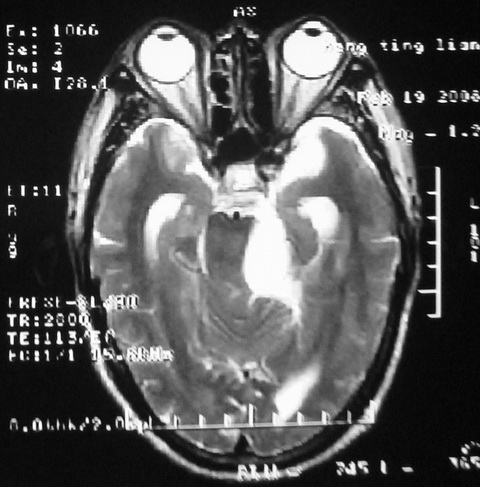

m,72,头疼,头晕两年,伴视力模糊三月,饮食呛咳两天。pe:颈部抵抗,左眼突出,左眼瞳孔约3mm,对光反射消失,双眼失明,伸舌困难,双肺呼吸音粗,心率110次/分,左上肢肌力i级,左下肢屈曲,肌张力高。现有08年2月19mri平扫及10年2月8日mri增强请会诊。ct病灶呈低密度伴散在点、片状等密度区,无明确钙化(无ct片资料可供上传)。[

脑外肿瘤,表皮样囊肿可能性大。

脑外肿瘤,病灶呈匍匐蔓延,表皮样囊肿可能性大。

脑外肿瘤,病灶呈匍匐蔓延,表皮样囊肿可能性大。支持!